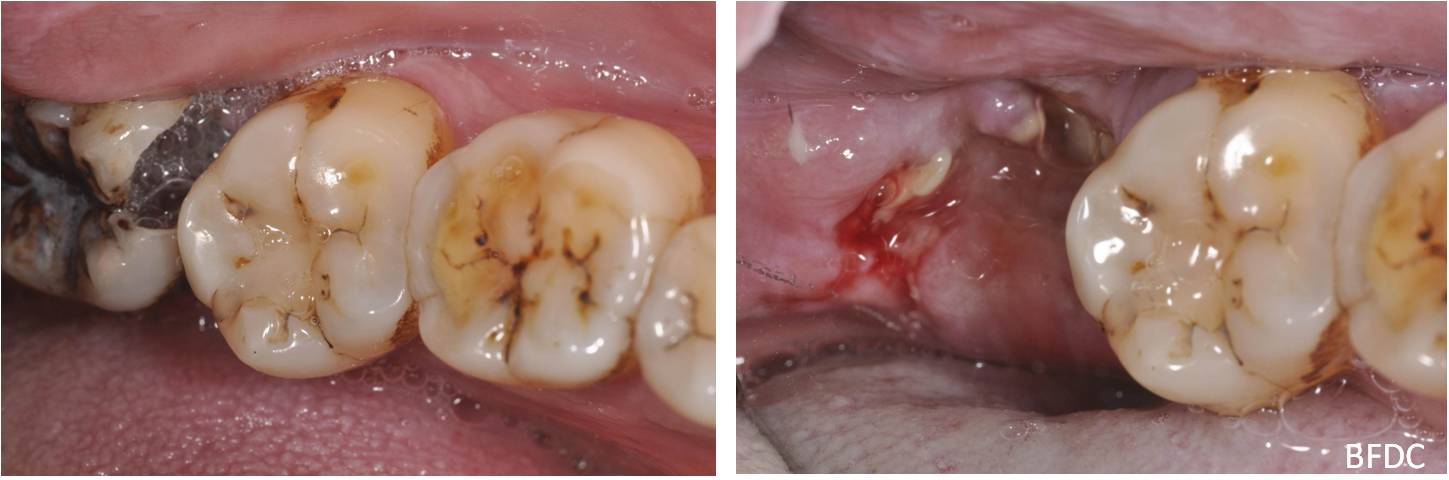

拔牙後傷口處理-阻生齒蛀牙-#38

口腔外科

拔牙後傷口處理